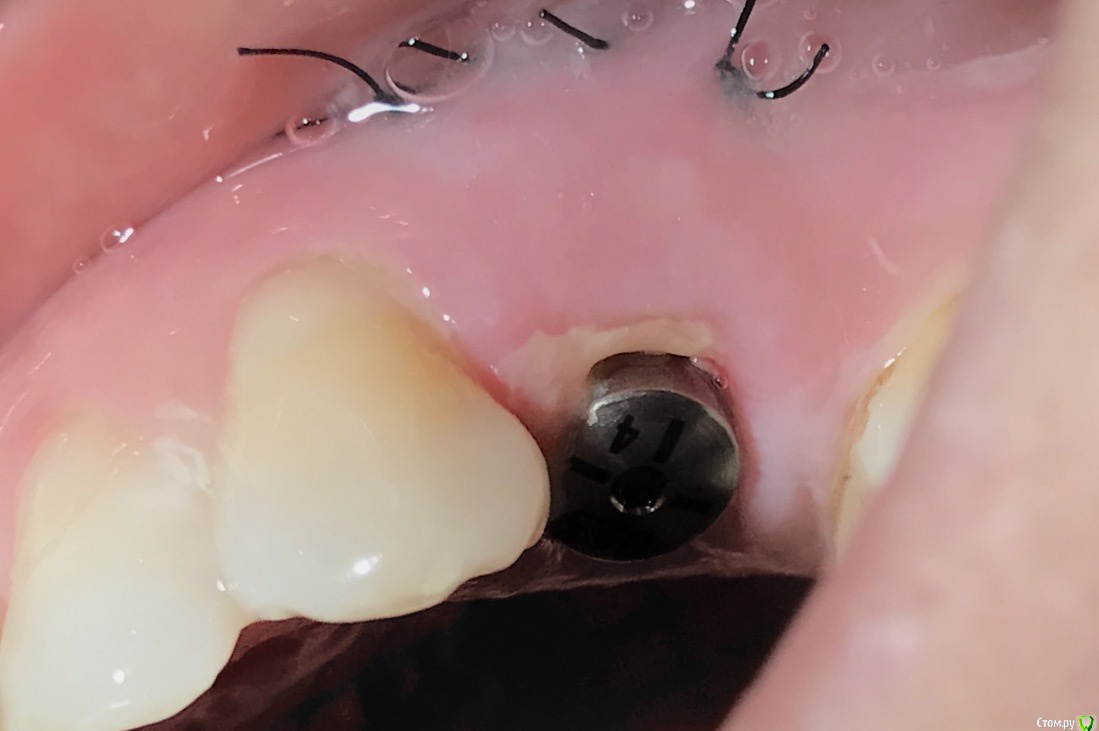

колесников Опубликовано 25 февраля, 2017 Поделиться Опубликовано 25 февраля, 2017 Здравствуйте коллеги! Представляю вашему вниманию этот клинический случай.В ноябре 2016 обратилась пациентка с жалобами на выпадение ортопедической конструкции в обл 24. Объективно: корни 24 не состоятельны. ,на десневом крае в проекции 24 свищевой ход с гнойным отделяемым.На КТ резорбция вестибулярной компактной пластинки и деструкция костной ткани в области щёчного корня.Приняв во внимание крайне негативное отношение пациентки к каким бы то ни было хирургическим вмешательствам и высоким эстетическим требованиям,было решено пойти на немедленную имплантацию .Снимки в день вмешательства,через 7,14 дней и 3мес.Имплант Astra tech profile 4.5х11мм. Сст с бугра вестибулярно. Вместо графта губки Коллапола (не вспомню причину,либо не было в наличии,либо отказ пациента). 15 Ссылка на комментарий

колесников Опубликовано 26 февраля, 2017 Автор Поделиться Опубликовано 26 февраля, 2017 Да,можно было ещё на 1мм притопить,и конечно графт вестибулярно оставить,но это стало понятно только сейчас. При постановке имплант был заглублен на 3 мм, посчитал что этого достаточно, но резорбция случилась больше планируемой. Первоначально планировалась нагрузка через 5 сут ,но ортопед позднее отказался от этой идеи. Думал заменить фдм на зебру,но пациентка пропала на 3 мес... Как получилось,так получилось. Торк был 35н/см,как обычно на астре. Ссылка на комментарий

Карен Аванесов Опубликовано 27 февраля, 2017 Поделиться Опубликовано 27 февраля, 2017 Гноем уже никого не испугаешь)) Чем обрабатывали рану перед внедрением имплантата? Ссылка на комментарий

колесников Опубликовано 27 февраля, 2017 Автор Поделиться Опубликовано 27 февраля, 2017 Как обычно,хлоргексидином промываю. Ну это нас не испугаешь,а у большинства коллег Робустова в голове. И именно по-этому теперь иногда делаю фотопротокол. Менталитет у нас такой,на слово не верят. Ссылка на комментарий